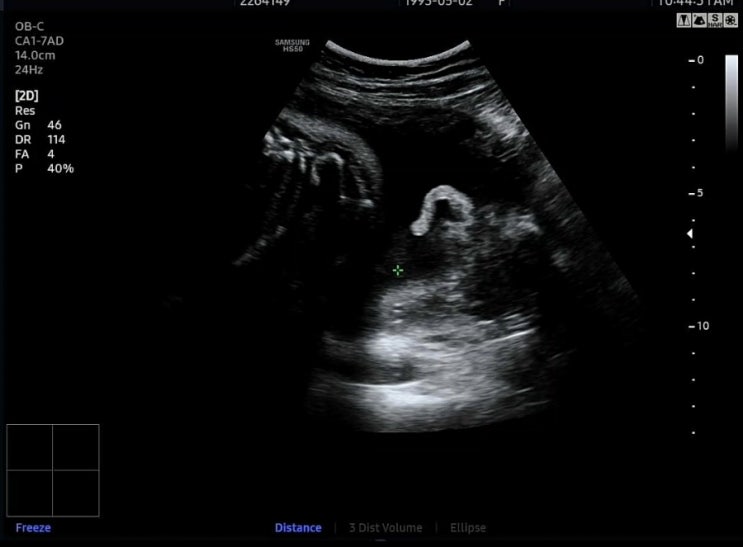

30주 정기검진받는날! 오전에 진료보러갔는데 울또복이가 자고있는 시간이라서 과연 초음파 잘 볼수있을지 ...